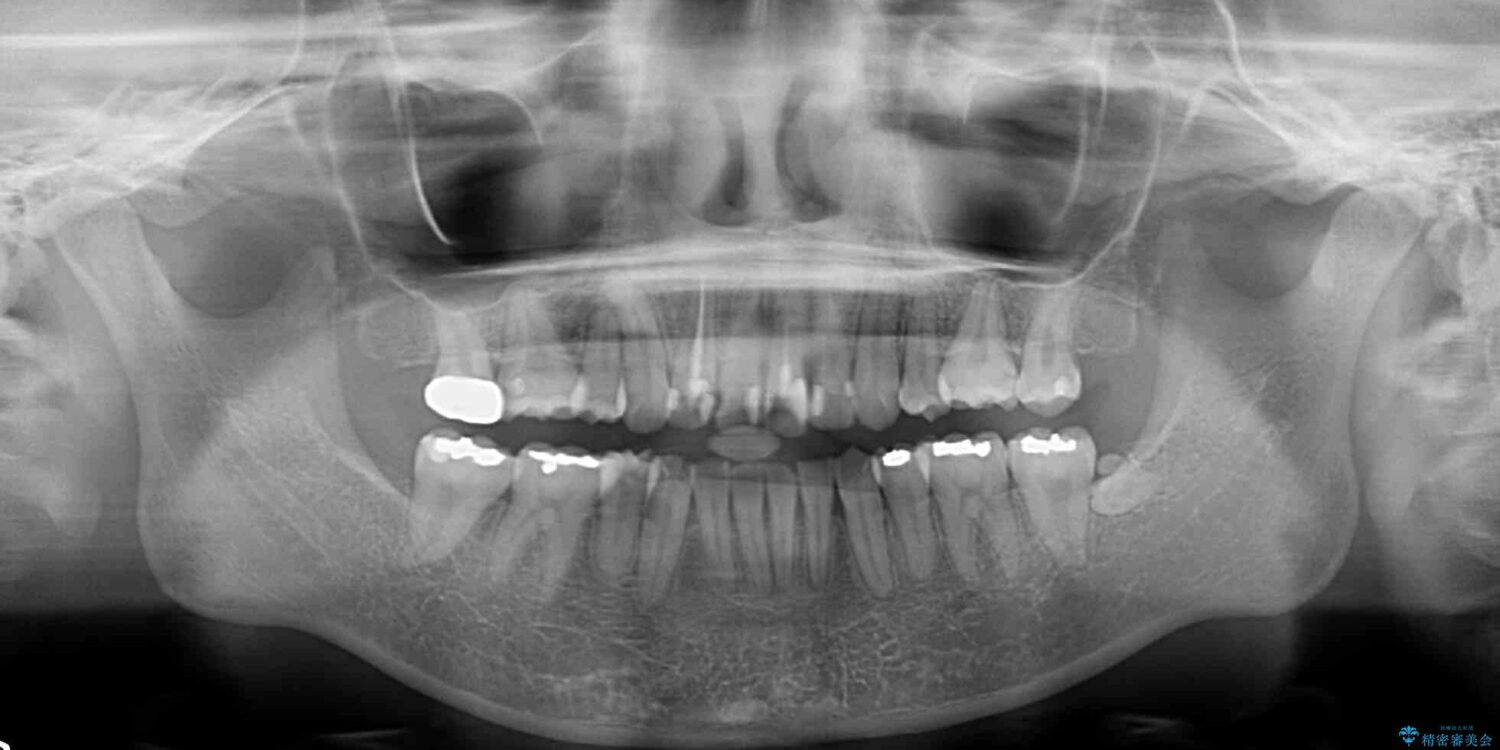

治療途中

• デコボコと深い咬み合わせ ワイヤー装置での抜歯矯正 治療途中画像

咬み合わせが深く、そのままでは上顎の抜歯スペースが閉じきらない可能性があったため、治療初期から深い咬み合わせを改善させるように試みました。

実際にはなかなか改善されず、当初予定よりも治療期間がやや長期化してしまいました。